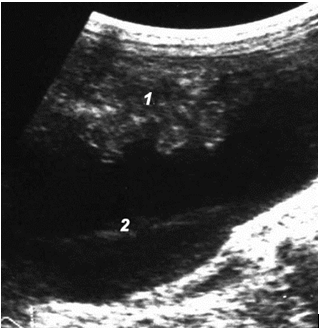

Нахождение жидкости еще и под передней брюшной стенкой в области мезогастрия соответствует «большому» гемоперитонеуму с объемом крови в брюшной полости более 26,7 мл/кг массы тела (рис. 13).

Рис. 13. «Большой» гемоперитонеум: 1 – петли тонкой кишки; 2 – кровь.